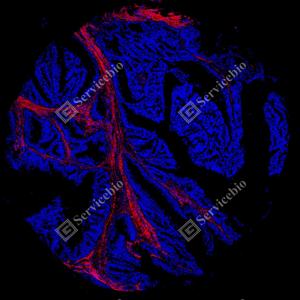

| IF检测Collagen III蛋白(货号 GB155674)(红色). 样品: 人结肠癌, 4%多聚甲醛 (货号G1101) 固定12-24小时. 抗原修复: 抗原修复仪 (货号 ARI-4),Tris-EDTA抗原修复液(pH 9.0) (货号G1203), 水浴100℃, 25分钟. 封闭: 3% BSA(货号GC305010)的PBS溶液, 室温孵育30分钟. —抗: 1: 500稀释, 4℃ 孵育过夜. 二抗: Cy3标记山羊抗小鼠IgG (H+L) (货号GB21301), 1: 300稀释, 室温孵育1小时. |

| IF检测Collagen III蛋白(货号 GB155674)(红色). 样品: 人子宫内膜癌, 4%多聚甲醛 (货号G1101) 固定12-24小时. 抗原修复: 抗原修复仪 (货号 ARI-4),Tris-EDTA抗原修复液(pH 9.0) (货号G1203), 水浴100℃, 25分钟. 封闭: 3% BSA(货号GC305010)的PBS溶液, 室温孵育30分钟. —抗: 1: 500稀释, 4℃ 孵育过夜. 二抗: Cy3标记山羊抗小鼠IgG (H+L) (货号GB21301), 1: 300稀释, 室温孵育1小时. |

| IF检测Collagen III蛋白(货号 GB155674)(红色). 样品: 人胃癌, 4%多聚甲醛 (货号G1101) 固定12-24小时. 抗原修复: 抗原修复仪 (货号 ARI-4),Tris-EDTA抗原修复液(pH 9.0) (货号G1203), 水浴100℃, 25分钟. 封闭: 3% BSA(货号GC305010)的PBS溶液, 室温孵育30分钟. —抗: 1: 500稀释, 4℃ 孵育过夜. 二抗: Cy3标记山羊抗小鼠IgG (H+L) (货号GB21301), 1: 300稀释, 室温孵育1小时. |

| IF检测Collagen III蛋白(货号 GB155674)(红色). 样品: 人肺癌, 4%多聚甲醛 (货号G1101) 固定12-24小时. 抗原修复: 抗原修复仪 (货号 ARI-4),Tris-EDTA抗原修复液(pH 9.0) (货号G1203), 水浴100℃, 25分钟. 封闭: 3% BSA(货号GC305010)的PBS溶液, 室温孵育30分钟. —抗: 1: 500稀释, 4℃ 孵育过夜. 二抗: Cy3标记山羊抗小鼠IgG (H+L) (货号GB21301), 1: 300稀释, 室温孵育1小时. |